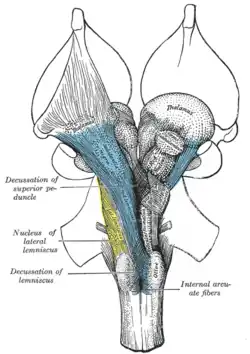

Deep dissection of brain-stem. Ventral view.

Deep dissection of brain-stem. Ventral view. -